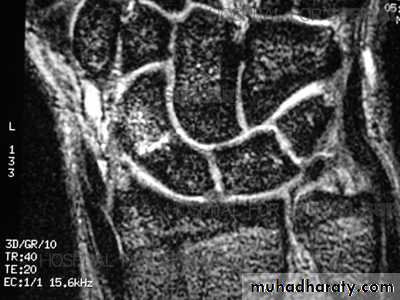

Scaphoid fractures:Its account for almost 75% of all carpal fractures, its rare in the elderly and children.

Avascular necrosis: the proximal fragment may die, especially with proximal pole fracture. It appears dense on X-ray after 2-3 months.Non-union: if the fracture is not united after 3 months.